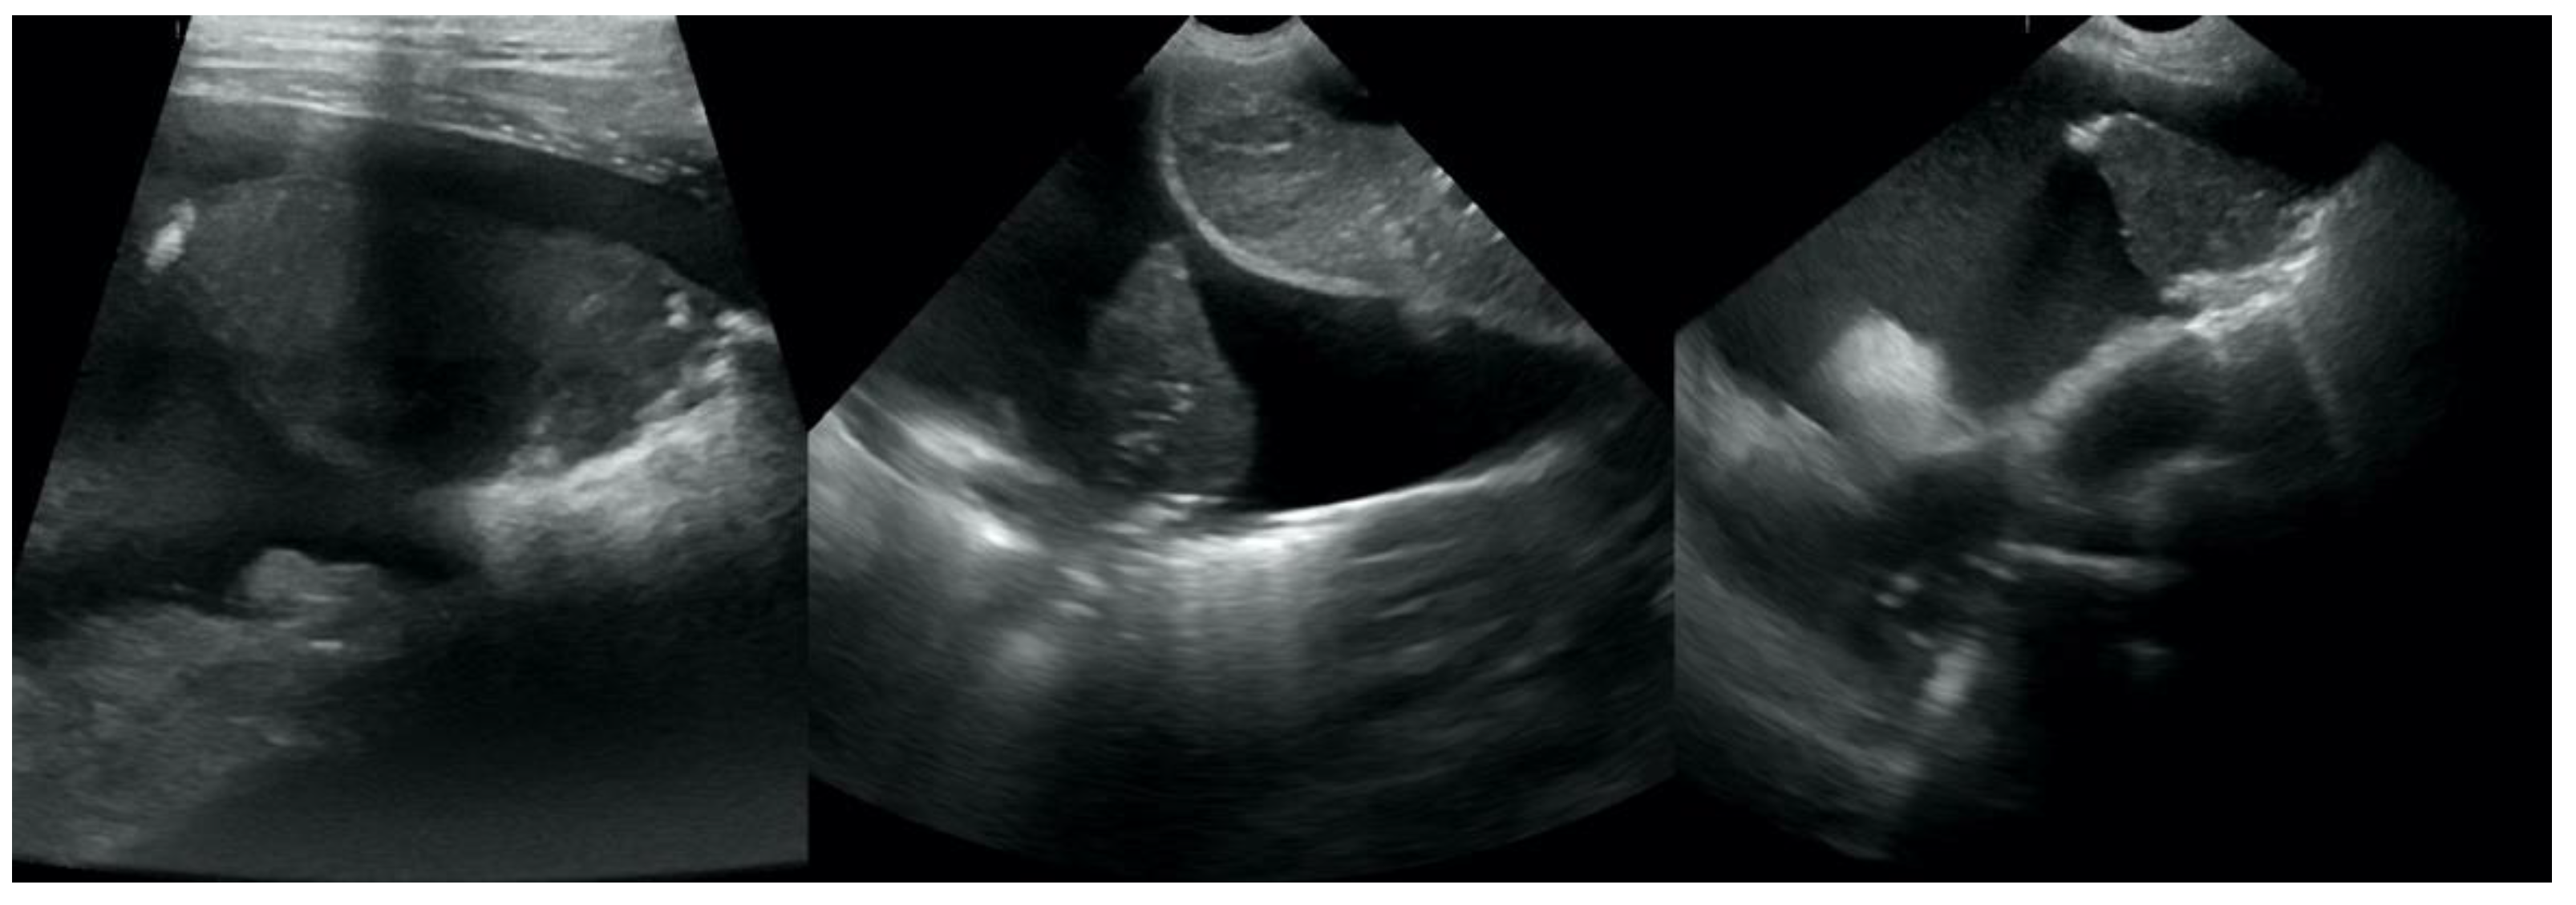

• Translobar consolidation producing tissue-like sign, henceforth referred to as hepatization (Figure 5, Figure 6 and Figure 7);

Figure 5. Hepatization without aeration in the course of pneumonia.

Figure 6. Hepatization without aeration in the course of lung cancer.

Figure 7. Hepatization with aeration in the course of pneumonia (AC) and lung cancer (D).